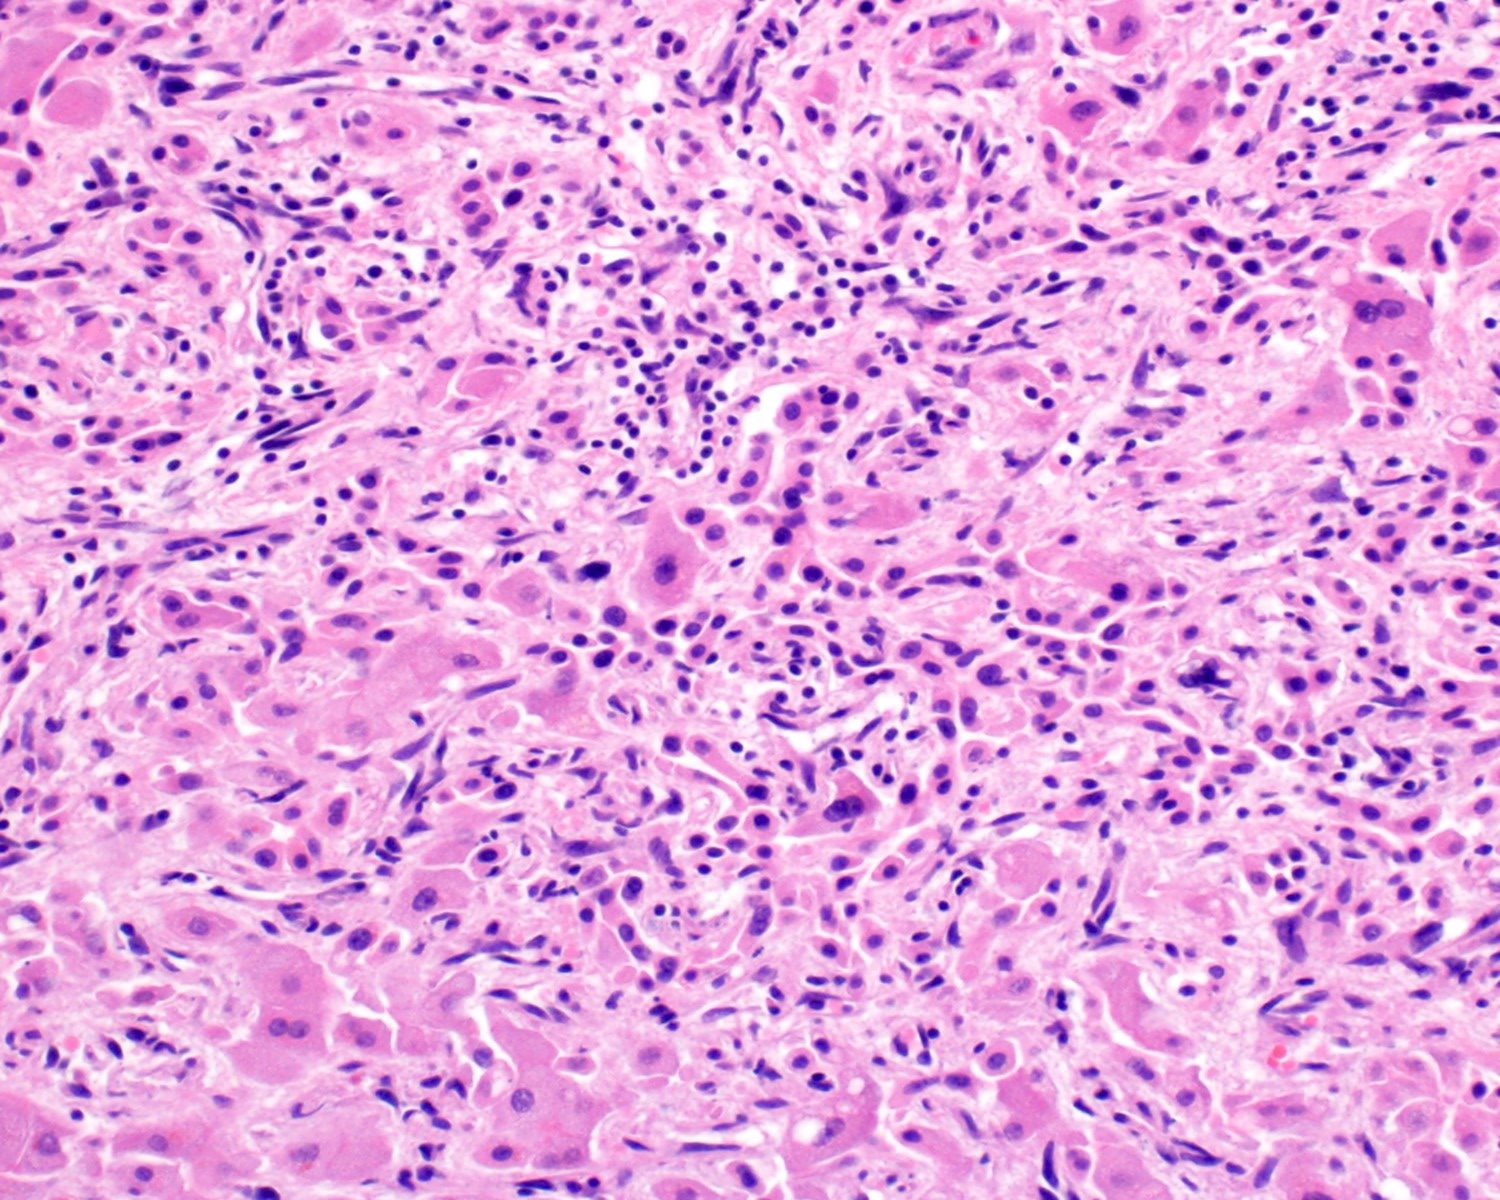

Microscopic (histologic) description

- 2 main histologic growth patterns were described (Am J Surg Pathol 2019;43:581)

- Non-mass forming

- Sinusoidal

- Dilated sinusoids lined by atypical endothelial cells seen in angiosarcoma with hyperchromatic nuclei

- Peliotic

- Blood pools and fibrin surrounded by hepatocytes

- Peripheral clusters of atypical endothelial cells seen in angiosarcoma mixed with inflammatory cells may extend into the sinusoids

- Mass forming

- Vasoformative shows architectural complexity and interconnecting vascular channels

- Anastomosing vessels and haphazard vascular channels

- Endothelial cells show tufting, atypia and mitotic figures

- Nonvasoformative shows epithelioid to spindled morphology

- Epithelioid morphology (epithelioid angiosarcoma) is most common (Am J Surg Pathol 2004;28:298)

- Solid nests or sheets of tumor cells

- Tumor often invades into sinusoids and hepatic venules at the periphery

- Cells have eosinophilic cytoplasm and oval nuclei

- Chromatin can be vesicular

- Multinucleated giant cells can be present

- Unusual growth patterns (Am J Surg Pathol 2019;43:581)

- Whorls of spindle cells in a background of chronic inflammation and loose myxoid to sclerotic stroma

- Infantile hemangioma-like angiosarcoma

- Hemangioma-like angiosarcoma

A 55 year old man presents with abdominal pain, weight loss and hepatomegaly. Laboratory studies reveal elevated liver enzymes but normal alpha fetoprotein levels. A liver core needle biopsy is performed. ERG immunohistochemistry is shown in the second image above. What is the most likely diagnosis?

E. Liver angiosarcoma. The histopathology shows nests and sheets of highly atypical neoplastic cells with hyperchromatic and pleomorphic nuclei, which are highlighted by ERG immunohistochemistry in the second image above. This makes liver angiosarcoma the most likely diagnosis.